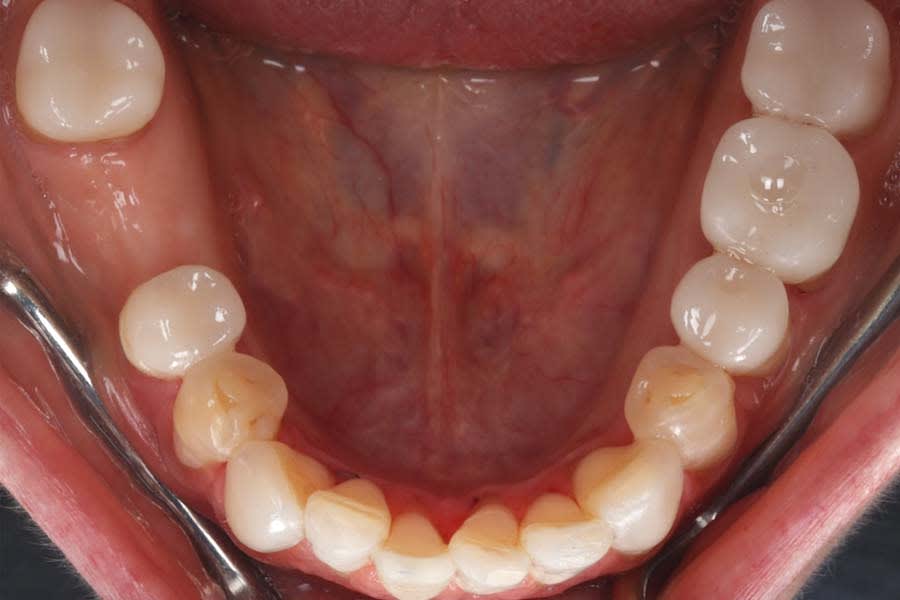

Intraoral and extraoral photographs and digital scans were obtained. Bite registration was taken in centric relation, along with three additional registrations at 1 mm, 1.5 mm, and 2 mm increased OVD using a leaf gauge. Medical and dietary history revealed mild gastric reflux and habitual tea consumption. Clinical examination identified multifactorial wear, with signs of intrinsic and extrinsic erosion, attrition, and abrasion (Figure 3 and Figure 4). There was significant tooth structure loss and partial dentoalveolar compensation. The gingival phenotype was thin, with RT1 recession defects at multiple sites.27

Definitive digital scans of each arch were obtained (Figure 7 and Figure 8), and the definitive restorations were designed based on the diagnostic wax-up (Figure 9). The design files were then exported in standard tessellation language (STL) format and transferred to the in-house technicians for milling of the definitive restorations in lithium-disilicate material. The restorations were subsequently custom-stained and glazed (Figure 10). Based on the patient’s esthetic preferences, modifications were made to the maxillary anterior design before delivery. The definitive restorations were evaluated intraorally and bonded with a luting composite (soft white shade) (Variolink® Esthetic LC, Ivoclar) (Figure 11), with all excess cement carefully removed (Figure 12 and Figure 13). The mandibular incisors were restored with direct composite, and abrasion lesions in the esthetic zone, intended for future root coverage, were provisionally restored with supragingival flowable composite for improved appearance (Figure 14).